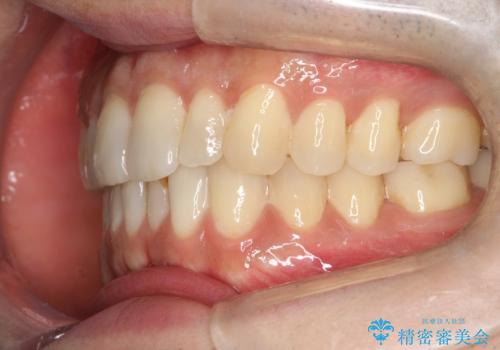

初診時の歯並びの状態としては、下顎に中等度のがたつき(叢生)がある状態でした。

抜歯は行わず下顎の奥のスペースを利用して歯をスライドする方法の他に親知らずの抜歯そして上下ともに歯列弓の拡大やディスキング(歯と歯の間の隙間を作る処置)を行い叢生を改善しました。

歯の大きさの不揃いが原因の正中のズレは、ディスキング量を調整することで合わせました。

矯正装置としてはマウスピースを使用しています。

見た目、嚙み合わせ及び、治療期間や施術内容に大変ご満足いただきました。